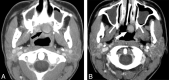

Fig 4.

Axial postcontrast CT images demonstrate 2 other examples of patients status post maxillectomy for tumor resection, with Trusoft obturators (arrows) containing trapped internal foci of air.